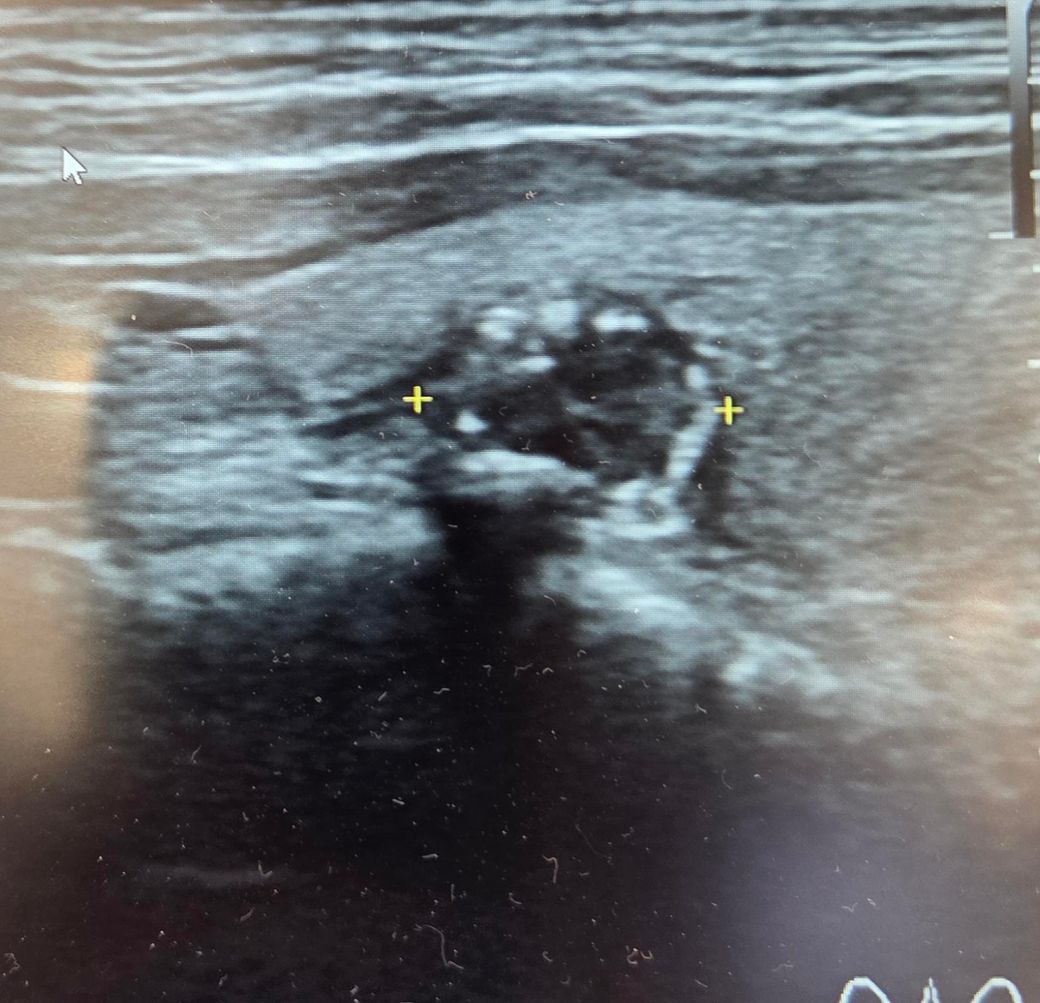

두번째 사진이 문제인데요.. 낭종이었는데 2년만에 석회화가 진행되었어요ㅜ 크기는 0.8센티로 변화는 없는데 세침해봐약겠죠?

• 2번 째 사진

갑상선 결절의 조직검사를 고려하는 경우는 갑상선 결절이 악성 즉 암인 가능성이 있는지에 따라

결정하게 됩니다. 초음파상 세로로 긴 모양,저음영,경계가 불규칙한 결절,미세석회화나 결절 주변부

석회화가 있는 경우는 악성 결절 가능성이 있어 생검을 고려할 수 있습니다. 좌측 사진은 단순 낭종으로

보이지만 우측 사진은 고형성분이 포함되어 있는 결절이며 주변부 석회화가 있어 생검을 고려해야 합니다.

따라서 세침 흡인 검사가 가능한 병원 내원하여 검사를 하는 것을 권해드립니다.

그렇습니다. 갑상선초음파에 대해서 잘 아시네요

말씀하신 병변은 세침검사를 통하여 확인을 해보셔야 하겠습니다.